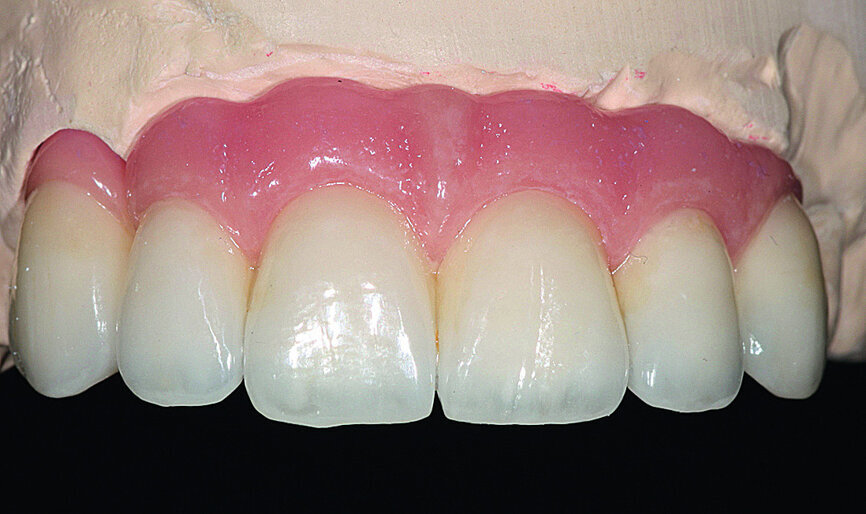

Pre-implant prosthetic study

After four months, according to radiographic examination, the tissue had healed and the bone mass appeared stable (Fig. 10). New impressions were taken to prepare for the next step in treatment: the implant drilling guide. After four months of healing, the increased vestibular bone volume allowed positioning the teeth at the crestal bone and reduction of the false gingiva using additional wax (Fig. 11). A key of the added wax was taken and fabricated in clear casting resin. The implant positions were decided on and finalised by drilling placement holes, determining the exact position of the implants (Fig. 12). The correct positioning of implants in relation to the future prothesis is an important prerequisite for aesthetic and functional success.

The cosmetic material (UNIFAST III resin; surface rendering: OPTIGLAZE color, GC Tech.Europe) was then placed on the framework (Fig. 27). The bone graft permitted a maximum reduction of the vestibular false gingiva.